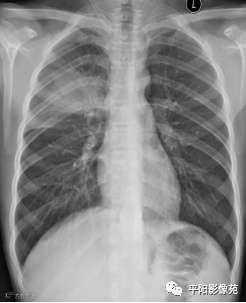

入院X线片:

影像特征:X线片右肺中上野片状高密度影,下缘以叶间裂为界,上缘及外侧缘模糊;CT位于右肺上叶后段,呈片状实变影,内见支气管影,边缘模糊。

影像诊断:右肺上叶大叶性肺炎。